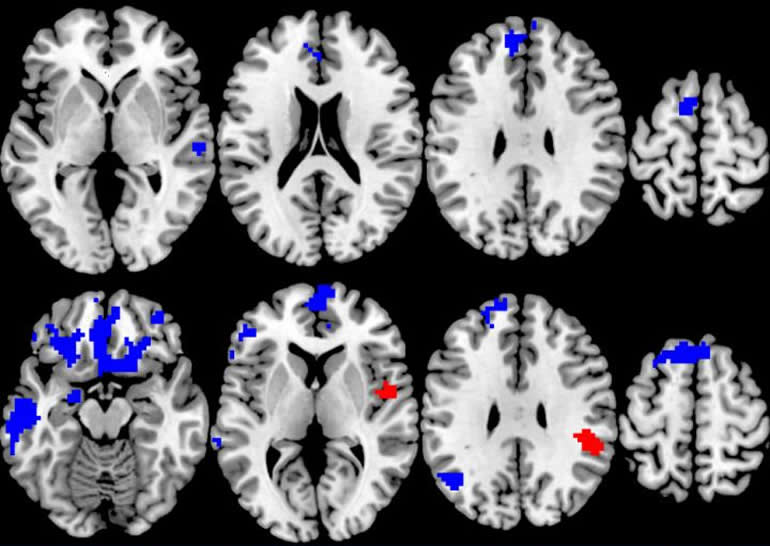

C’est exactement ce que montre les neurosciences : le cerveau se remodèle